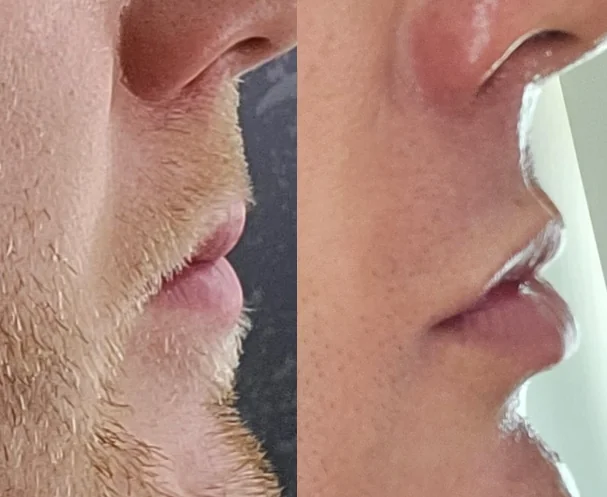

Before we jump into it I wanna show the importance of having a nice nasolabial or simply put "philtrum" curve.

It's what makes a side profile balanced - not hyper masculine but "pretty" to look at - angularity and curves in the right places make the side profile beautiful.

Case study #1)

Yes this isn't a true side profile but we can still compare as the orientatation is similar.

A dead giveaway is the Nasolabial angle becoming more acute - this means the nasal spine and the A point haven't moved as one and thus the relationship has changed.

Case study #1)

Yes this isn't a true side profile but we can still compare as the orientatation is similar.

A dead giveaway is the Nasolabial angle becoming more acute - this means the nasal spine and the A point haven't moved as one and thus the relationship has changed.